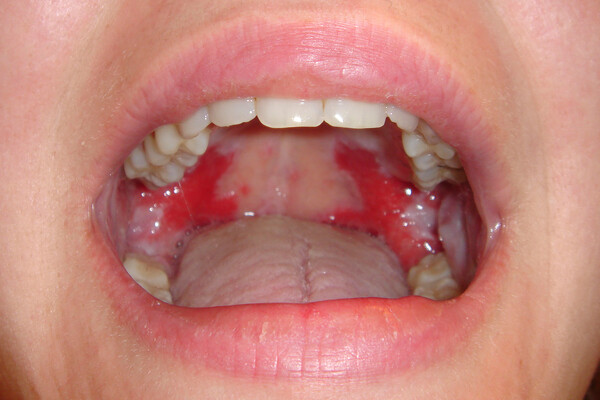

What Causes Red Spots On The Roof Of Your Mouth?

Red spots on the roof of your mouth can be caused by a variety of different reasons. Some are just a minor inconvenience, while others could be a sign of a more serious health issue that may require further investigation. Here are some common possibilities:

In rare cases, oral sores or lesions can be a sign of oral cancer, so it is important to have any spots that are painful, cause difficulty in eating or drinking or do not heal quickly checked by your dentist.